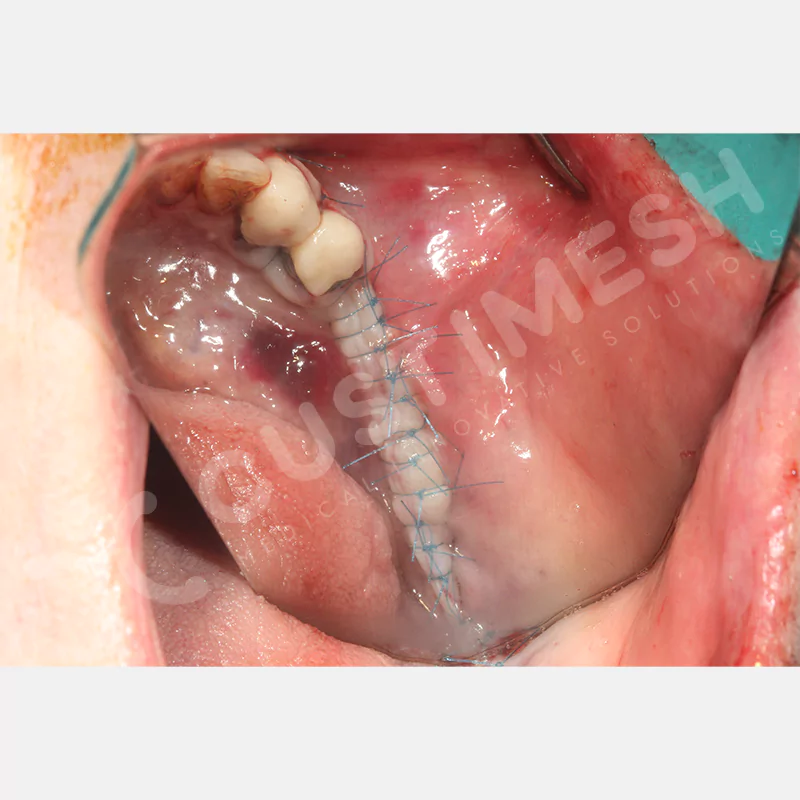

VAKA 1